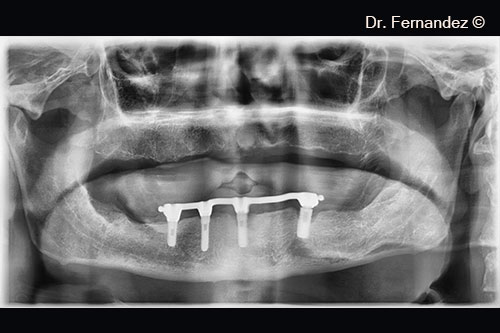

Initial radiological appearance